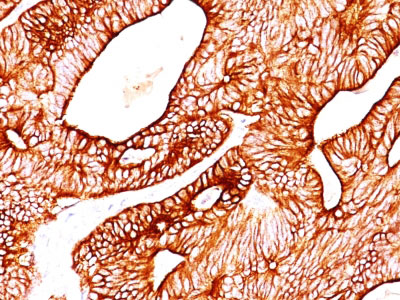

Formalin-fixed, paraffin-embedded human Lung Carcinoma stained with Cytokeratin 8/18 Monoclonal Antibody (KRT8/803 + KRT18/835).

Formalin-fixed, paraffin-embedded human Ovarian Carcinoma stained with Cytokeratin 8/18 Monoclonal Antibody (KRT8/803 + KRT18/835).

Formalin-fixed, paraffin-embedded human Colon Carcinoma stained with Cytokeratin 8/18 Monoclonal Antibody (KRT8/803 + KRT18/835). |

Cytokeratin 8 (CK8) belongs to the type II (or B or basic) subfamily of high molecular weight cytokeratins and exists in combination with cytokeratin 18 (CK18). This MAb cocktail recognizes all simple epithelia including glandular epithelium, for example thyroid, female breast, gastrointestinal tract, respiratory tract, and urogenital tract including transitional epithelium. All adenocarcinomas and most squamous carcinomas are positive but keratinizing squamous carcinomas are usually negative. This antibody is useful in demonstrating the presence of Paget cells; there is very little keratin 18 in the normal epidermis so only Paget cells are stained.?Immuno-histochemical staining with this MAb is indistinguishable from that obtained with monoclonal antibody 5D3.